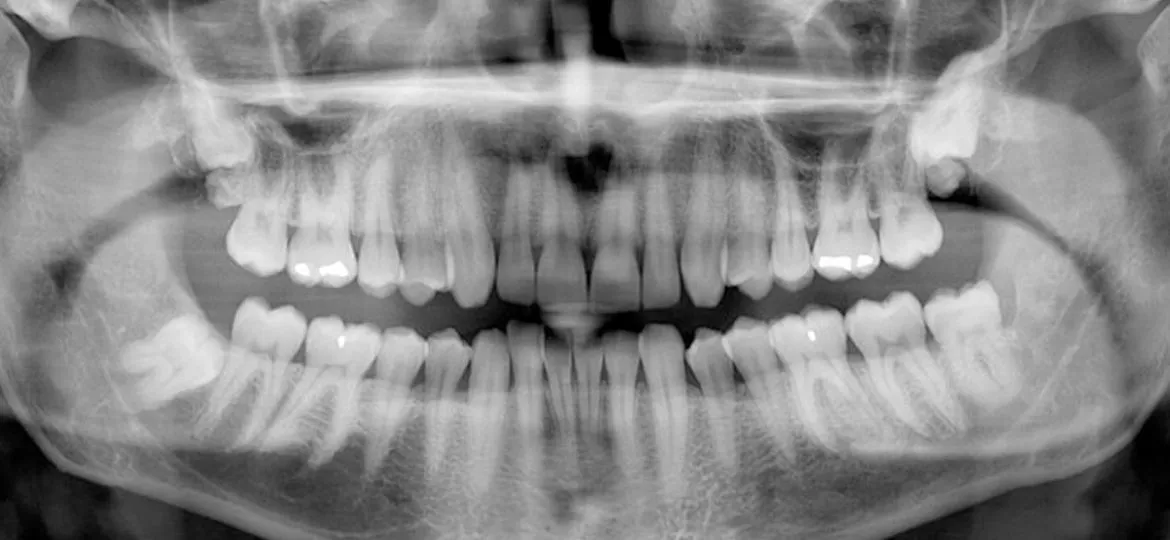

- Evaluar fotografías, radiografías o estudios previos